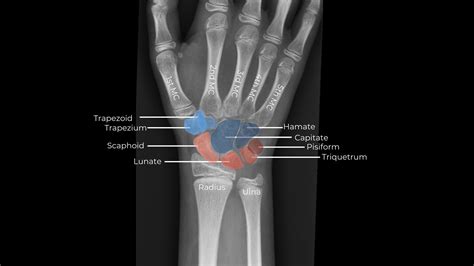

The wrist is a complex structure composed of multiple bones, ligaments, and tendons. It connects the hand to the forearm and allows for a wide range of movements. The primary bones in the wrist include:

• Carpal Bones: There are eight carpal bones in the wrist, arranged in two rows. These bones are small and irregularly shaped, providing stability and flexibility to the wrist.

• Metacarpal Bones: These five bones connect the carpal bones to the phalanges (finger bones).

• Radius and Ulna: These are the two bones of the forearm that articulate with the carpal bones to form the wrist joint.